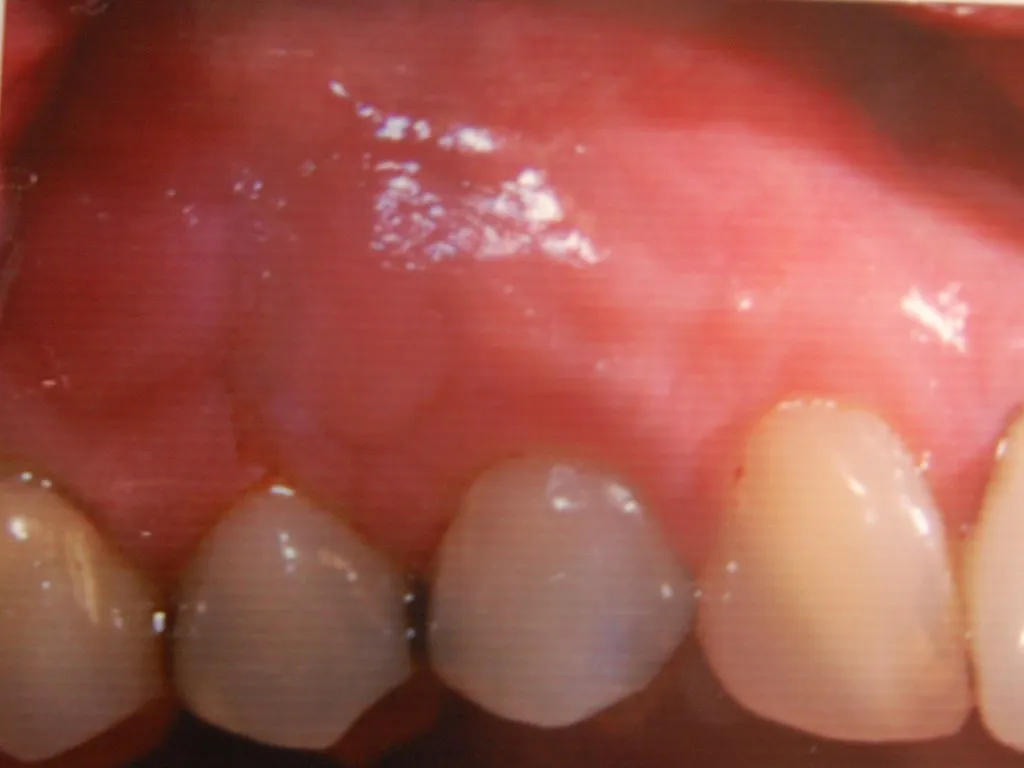

Guided Tissue Regeneration with Bone Graft & Growth Factors to Save teeth